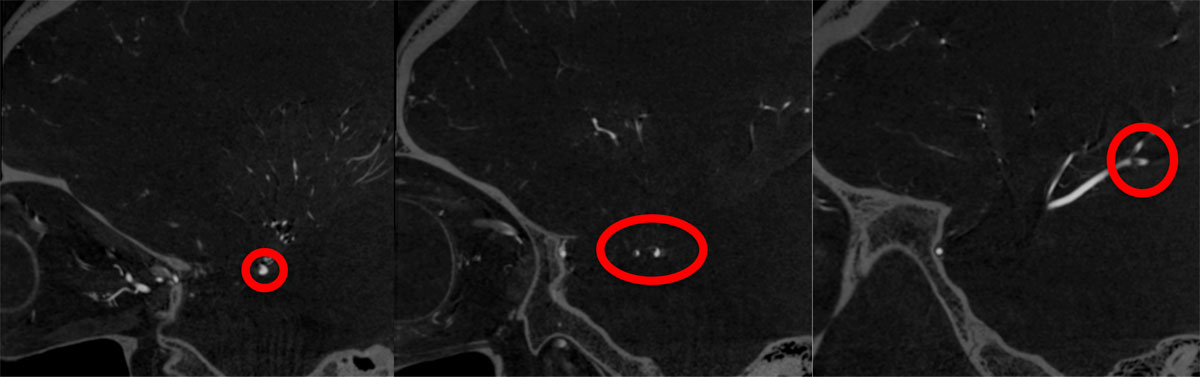

CT – CTA - CTP